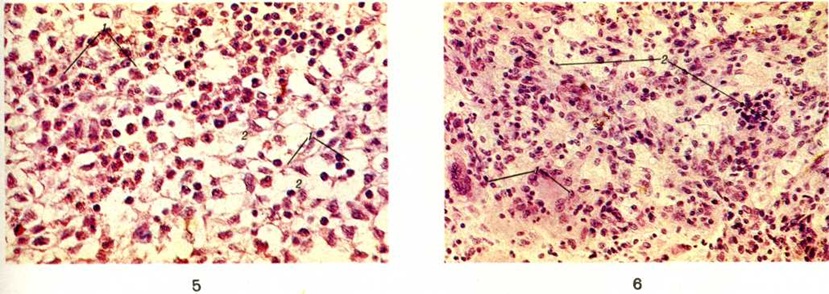

Микроскопически опухолевидные гранулематозные разрастания состоят из гистиоцитов с примесью рассеянных или лежащих в виде скоплений лимфоцитов, плазматических клеток, эозинофильных лейкоцитов, главным образом сегментоядерных. Могут встречаться сидерофаги (смотри полный свод знаний: Бурое уплотнение лёгких). Характерно наличие большого числа ксантомных (нередко гигантских многоядерных) клеток-макрофагов с пенистой вакуолизированной за счёт накопления холестерина и холестерин-эстеров цитоплазмой (цветной рисунок 5 и 6).Соотношение клеточных элементов может варьировать, что отражает разные стадии процесса. Цитоплазма гистиоцитов характеризуется суданофилией, диффузной ШИК-положительной реакцией (смотри полный свод знаний: ШИК-реакция), высокой активностью гидро лаз. При электронно-микроскопическом исследовании в цитоплазме гистиоцитов выявляются так называемый тельца X — удлинённые включения, связанные с мембраной клеток, сходные с лизосомоподобными гранулами клеток Лангерганса шиповатого слоя эпидермиса. Как правило, имеются очаги некроза, кровоизлияния и в поздней стадии — поля склероза.

Рис. 5 —6. Микропрепараты опухолевидных гранулематозных разрастаний в костной ткани при болезни Хенда—Шюллера—Крисчена (соотношение клеточных элементов отражает различные стадии процесса); окраска гематоксилин-эозином; X 400.

Рис. 5. На более ранней стадии процесса в гранулематозных разрастаниях преобладают гистиоциты (1) и ксантомные клетки (2). Рис. 6. На более поздней стадии процесса появляются многоядерные гигантские клетки (1) и участки склероза (2).